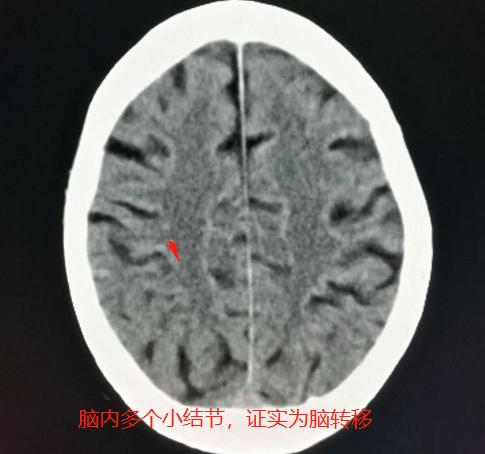

病例3. 女性患者,83岁,突发头晕、言语不清1天,怀疑脑血管意外做颅脑CT:

发现脑内多发的小结节,比周围脑组织密度略高,但周围没有低密度水肿带。

询问病史,老人没有去过疫区,也没有吃过生猪肉等,不支持寄生虫病,那就要想到不典型脑转移瘤的可能,于是住院进一步检查肺部:

发现了右下肺癌,伴有肺底部膈胸膜牵拉,符合肺癌并脑多发转移瘤。